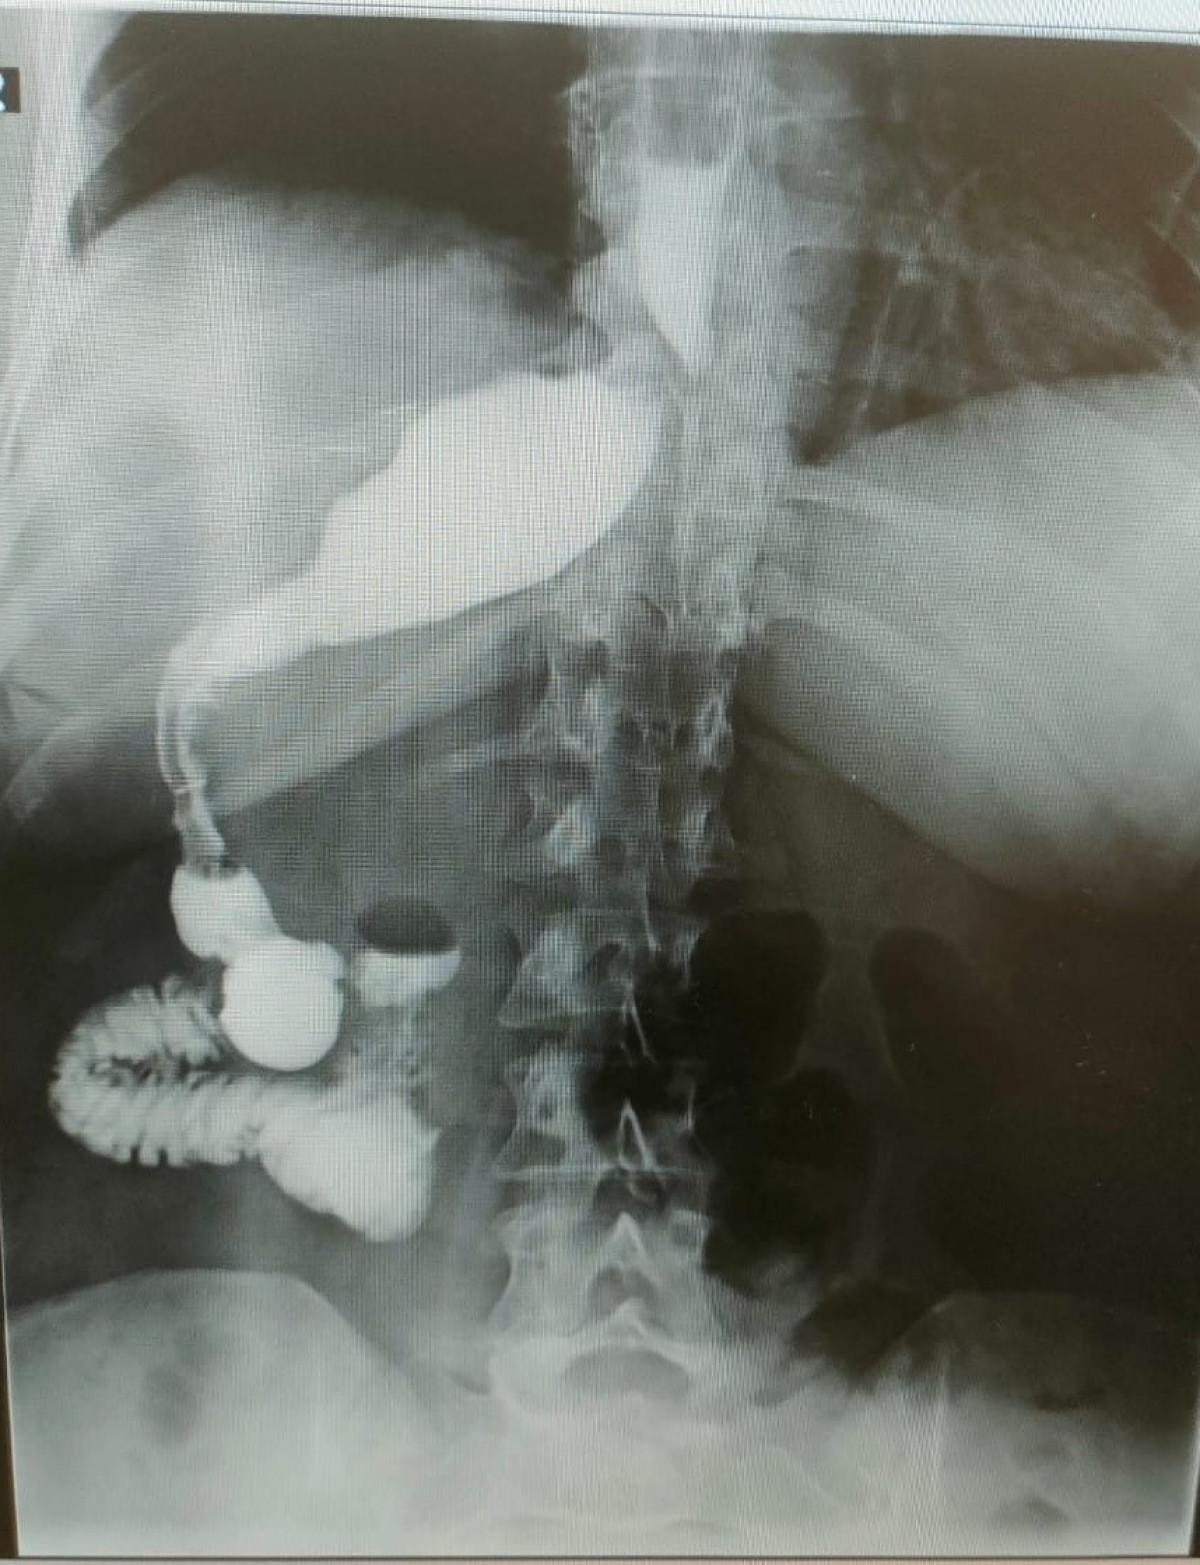

Almanya'dan tüp mide ameliyatı olmak için Antalya'ya gelen 46 yaşındaki hemşire Antje Kirscht, eşine az rastlanır bir tıbbi durumla karşılaştı. Antalya'da özel bir hastanede gerçekleştirilen operasyon sırasında Kirscht'in midesini olması gerektiği yerde göremeyen doktorlar, kısa süren şaşkınlığın ardından mideyi karaciğerinin arkasında, sağ tarafta buldu. Mide başarılı bir operasyonla küçültülürken bu sıra dışı anatomik durumun, dünyada yalnızca 100 binde bir görüldüğü biliniyor.

Ameliyat esnasında cerrahi ekip, Kirscht'in midesini karaciğerinin arkasında, sağ tarafta buldu. Bu sıra dışı anatomik durum, hem hasta hem de ekibin şaşkınlık yaşamasına neden oldu.

Çok yapılan bu operasyonlar içerisinde hastanın değişik bir anomalisi vardı. 100 binde bir görüldüğü söyleniyor. Organların hepsi ters olabiliyor. Bu daha sık görülen bir şey ama bu hastada bütün organlar yerli yerinde ama sadece mide sağ tarafa kaymış. Yani karaciğerin arkasına gitmiş. Operasyona başladığımızda mideyi bulamadık. Karaciğeri kaldırınca mideyi sağ tarafta gördük. Bu çok nadir bir durum. 2023 yılı verilerine göre, böyle bir tüp mide ameliyatı dünyada yalnızca 50 kişiye uygulanmış. Biz de bu vakayı başarıyla gerçekleştirdik. Teknik açıdan bizi zorlayan ancak deneyimimizi artıran bir ameliyat oldu.

Prof. Dr. Gürkan, ameliyatın detaylarına değinerek, “Tüp mide operasyonunun ayna görüntüsünü yaptık. Normalde sol tarafta yaptığımız obezite ameliyatını bu hastada sağ tarafta gerçekleştirdik. Midenin karaciğerin arkasında olması ameliyat süresini 15 dakika uzattı ve toplamda 1 saat sürdü. Bizim için de hoş bir tesadüf oldu.” diye konuştu.